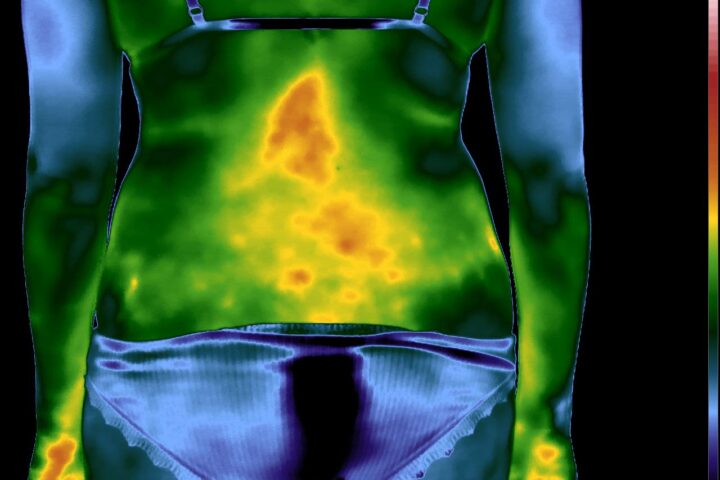

Como no caso do paciente abaixo do sexo masculino, 38 anos, sem comorbidades e que apresentou dor aguda em região lombar. Foi realizada uma Análise Termofuncional e foi detectado alterações térmicas compatíveis com o relato clínico de dor lombar.

Essas informações foram integradas à avaliação fisioterapêutica e, quando analisadas corretamente dentro da técnica, a termografia permite compreender respostas fisiológicas que não aparecem em exames estruturais.

Com formação adequada, ele identifica padrões fisiológicos relevantes para a prática clínica e é exatamente isso que a Técnica Termofuncional ensina.